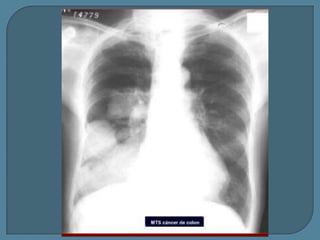

Metástasis de Ca. de colon

Tuberculosis: Nódulo cavitado con lesiones satélite en Rx y TC